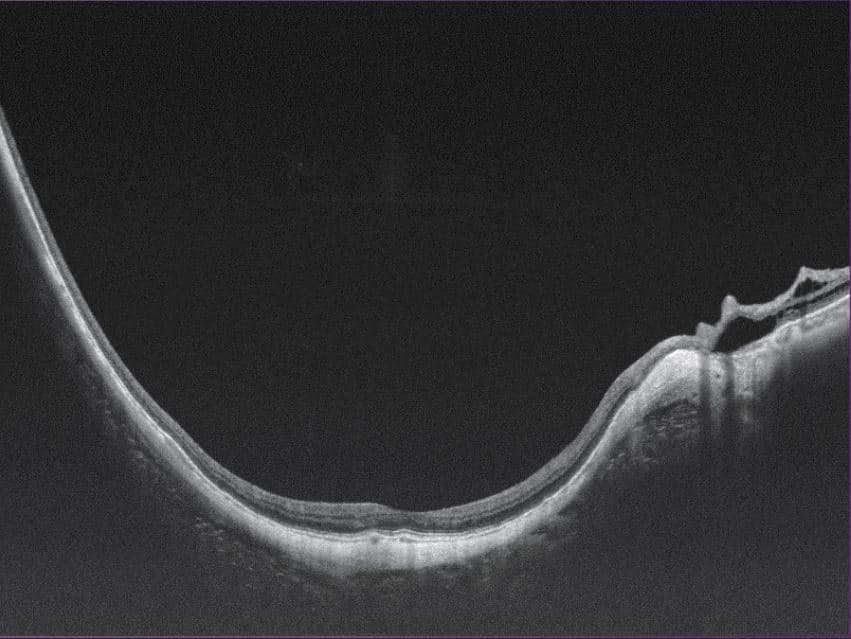

100kHz speed full-range swept-source OCT for anterior and posterior

- Full-Range wide-field Swept Source OCT